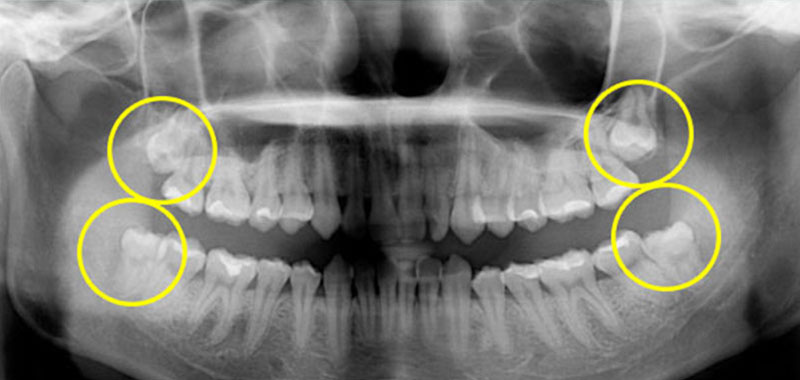

上下左右四顆智齒都卡住長不出來